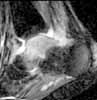

58 y/o female, had ankle sprain 3 months ago. First avulsion fracture on the tip of fibula was diagnosed and cast was applied for four weeks. After cast removal pain and swelling did not subside.

Now has mild swelling at ankle. Walks with cruches, weight bearing is not possible due to pain.

I think there was a nondisplaced talar neck fracture with complicated by AVN.

Current X-ray shows sclerosis of talar body, destruction at talar dome. MRI shows diffuse swelling in talus (interesting where comes the swelling if there is avascularity?). CT does not surely confirm fracture but shows diffuse osteoporosis in tarsal bones.